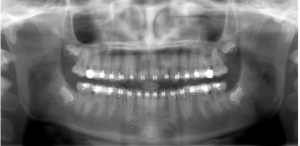

Impacted Teeth Exposed

After

Usually the impacted tooth is exposed over the course of a few months and brought into the correct position of the mouth. Correction of impacted teeth may involve a minor surgical procedure performed by an oral surgeon working closely with our practice. This will allow us to then guide eruption of the impacted tooth into proper position.